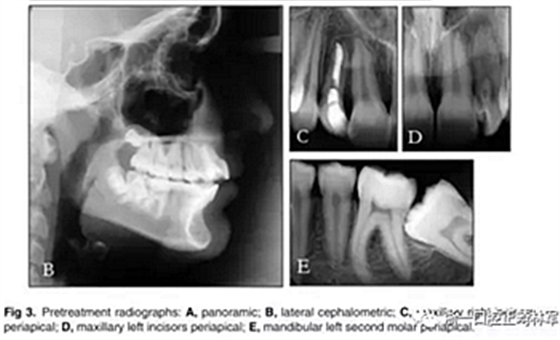

全景X線(圖3)顯示所有牙齒均存在,包括第三磨牙的牙胚。左下頜第二磨牙近中阻生。X線片顯示以前根管治療的上頜右側(cè)切牙(據(jù)報(bào)道有窩溝內(nèi)陷),對側(cè)切牙有根尖周圍病變以及窩溝內(nèi)陷的典型影像學(xué)表現(xiàn)。上頜中切牙的根部顯示先前存在的吸收。頭影測量分析顯示上頜骨和下頜骨矢狀和垂直關(guān)系正常。上頜和下頜門牙過度唇側(cè)傾斜。